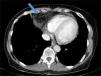

En vista de los resultados de la radiografía de tórax se decide solicitar TAC toracoabdominopélvica (fig. 2), que evidencia la presencia de una hernia de Morgagni con contenido graso omental y líquido a través del orificio herniario. Dicha herniación producía una atelectasia laminar a nivel del lóbulo medio, sin evidencia de adenopatías hiliomediastínicas ni axilares de tamaño/aspecto significativo. Con los resultados de la TAC se solicitó un peritoneograma, que descartó la presencia de fuga de líquido peritoneal o comunicación pleuroperitoneal. La paciente es valorada desde cirugía general realizándose el cierre quirúrgico del defecto herniario dada la sintomatología asociada, las potenciales complicaciones derivadas y la intención de mantener a largo plazo tratamiento renal sustitutivo con DP. Tras la cirugía pasa temporalmente a hemodiálisis. Al mes de la intervención, y ante la ausencia de complicaciones derivadas, la paciente reinicia tratamiento con DP con un intercambio nocturno. Progresivamente, la paciente ha ido perdiendo función renal residual, motivo por el cual ha sido necesario incrementar a 3 intercambios diarios, sin presentar complicaciones ni nuevas hernias.